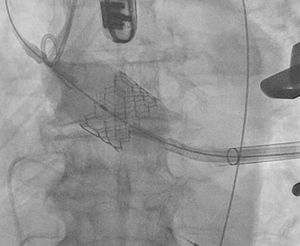

Existen numerosos escenarios que motivan el planteamiento de la post-dilatación tras el implante de una TAVI. Quizá el más importante (por su elevada frecuencia y repercusión negativa) sea la reducción de la severidad de una RPV, pues el baloneo promueve una expansión óptima de la prótesis (figs. 3 y 4). Con ello, también se consiguen un aumento del área valvular efectiva, una disminución de los gradientes y, en consecuencia, una reducción del mismatch (que se ha asociado a una mayor incidencia de trombosis valvular clínica y subclínica)46.

Regurgitación perivalvularLa RPV es consecuencia de una aposición incompleta de la prótesis al anillo nativo por intensa calcificación y excentricidad anular, infra, sobredimensión o posicionamiento inadecuado de la TAVI.

Aunque su incidencia ha disminuido progresivamente fruto de avances tecnológicos y optimización del procedimiento (actualmente la prevalencia de RPV moderada-severa es inferior al 5%)47, los implantes de última generación en poblaciones de bajo riesgo todavía exhiben una RPV moderada-severa a 30días del 0,8% en las TAVI balón-expandibles y del 3,4% de las autoexpandibles. Igualmente, la incidencia de RPV ligera sigue siendo muy elevada en este subgrupo de enfermos a 30días: del 29% en prótesis balón-expandibles y del 36% en autoexpandibles5,48.

La situación que más frecuentemente plantea la necesidad de post-dilatar es la existencia de una RPV (fig. 6). Quizá la envergadura de la misma (moderada/severa) sea uno de los factores más potentes, pero debemos atender también a otras características. Un paciente joven, de moderado/bajo riesgo, con anatomía favorable y sin comorbilidad o trastorno previo de la conducción se beneficiaría, sin duda, de la misma. También el implante de prótesis autoexpandibles, estenosis aórtica pura previa o aquellos casos en los que prima una gran durabilidad del implante.